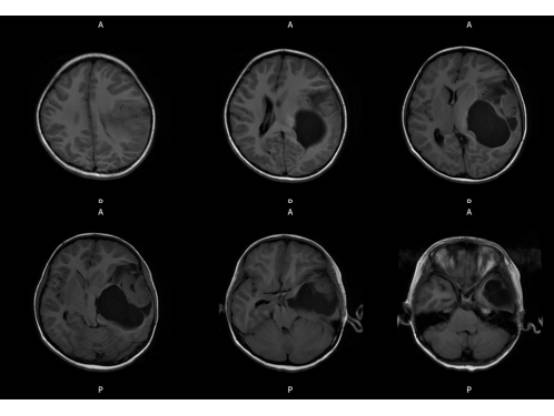

MR平扫及增强示:

MR

左侧颞叶见大块状等长T1等长T2异常信号,FLAIR呈高新,DWI(b=1000)实质部分呈稍高信号,ADC实质部分呈等信号,边界尚清,周围脑实质受压。注入GD-DTPA后病变实质部分呈明显强化。